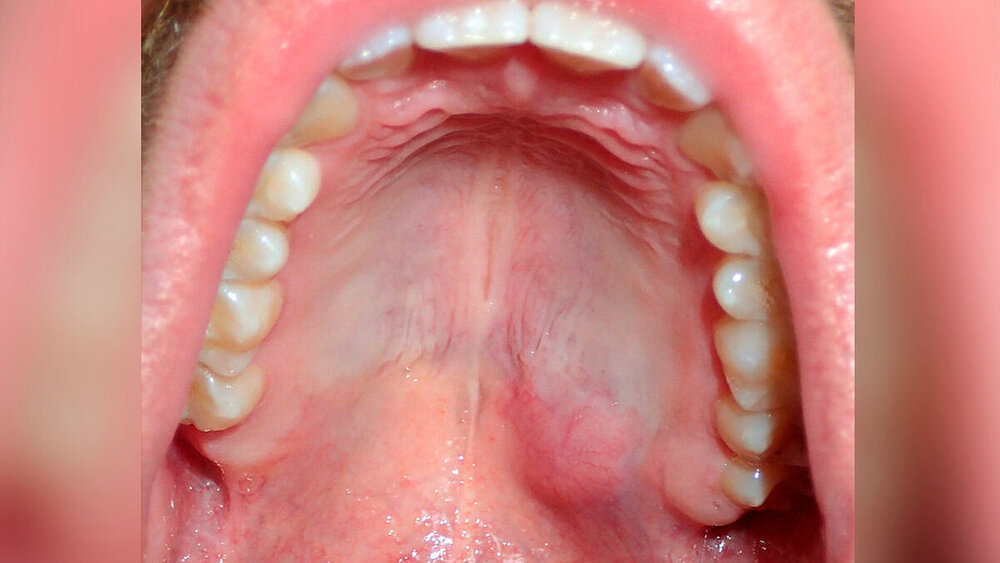

Klinisch zeigte sich eine derbe, nicht druckdolente und mit normaler Schleimhaut bedeckte Raumforderung im Bereich des Gaumens linksseitig (Abbildung 1). Die Zähne im Bereich des zweiten Quadranten zeigten keine pathologischen Befunde. Insbesondere die Zähne 26, 27 und 28 reagierten negativ auf die Perkussionsprobe und positiv auf die Sensibilitätsprobe mit Kälte. Im Röntgenzahnfilm und im Orthopantomogramm zeigten sich keine wegweisenden Befunde. Dennoch wurde von zahnärztlicher Seite ein entzündliches Geschehen vermutet.

Zur weiteren Klärung der Dignität des Befunds waren sowohl eine bildgebende Untersuchung als auch eine histopathologische weitere Diagnostik indiziert. Aufgrund des Weichteilcharakters des Befunds erfolgte in einem ersten Schritt eine Magnetresonanztomografie des Mittelgesichts mit Kontrastmittel. Es zeigte sich eine homogen begrenzte, kontrastmittelaufnehmende Raumforderung im Übergang zwischen hartem und weichem Gaumen ohne Zeichen einer Infiltration der Umgebungsstrukturen mit einem sagittalen Durchmesser von circa 3 cm. In der Zusammenschau der klinischen und bildgebenden Befunde bestand der Verdacht auf das Vorliegen eines pleomorphen Adenoms. Aufgrund der geringen Größe des Befunds wurde zur histologischen Sicherung der Diagnose eine Resektion in toto angestrebt.